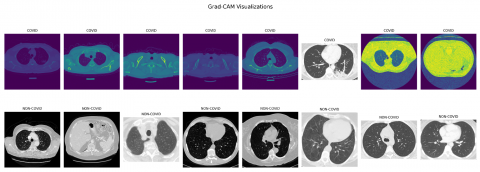

Overall, these metrics suggest that the model has high accuracy in diagnosing COVID-19 from chest CT scan images, with a relatively low rate of false positives (patients incorrectly diagnosed with COVID-19) and a very high rate of true positives (COVID-19 patients correctly diagnosed). To visualize our model's predictions, we have used the technique explained by algorithm 3 and is shown in Figure 7.

Figure 7. Grad-CAM visualizations for the predictions

The GradCAM display facilitates the identification of the most crucial areas in a CT scan towards prediction by the model. By visualizing these regions, we can gain insights into what features of the CT scan are most indicative of COVID-19, and potentially use this information to refine your model or develop new diagnostic tools. To further elucidate the capabilities of our GradCAM visualizations, we intend to integrate a detailed analysis of specific instances where our model precisely highlights the CT scan features characteristic of COVID-19.

Figure 7 demonstrates the model's focus, denoted by warmer colours, on regions known to be affected by the virus, such as areas showing ground-glass opacities and pulmonary consolidation. These visual cues are crucial for clinicians as they offer a non-intrusive means to understand the AI's reasoning, thereby making the model's predictions more transparent and trustworthy. By meticulously correlating the highlighted regions with actual symptoms and anomalies associated with COVID-19, we not only verify the model's diagnostic accuracy but also underline its potential as an assistive tool for medical professionals. This endeavour will bridge the current divide between automated diagnostic systems and their real-world clinical application, ensuring that our FL model is not just a black box but a supporter in healthcare decision-making.